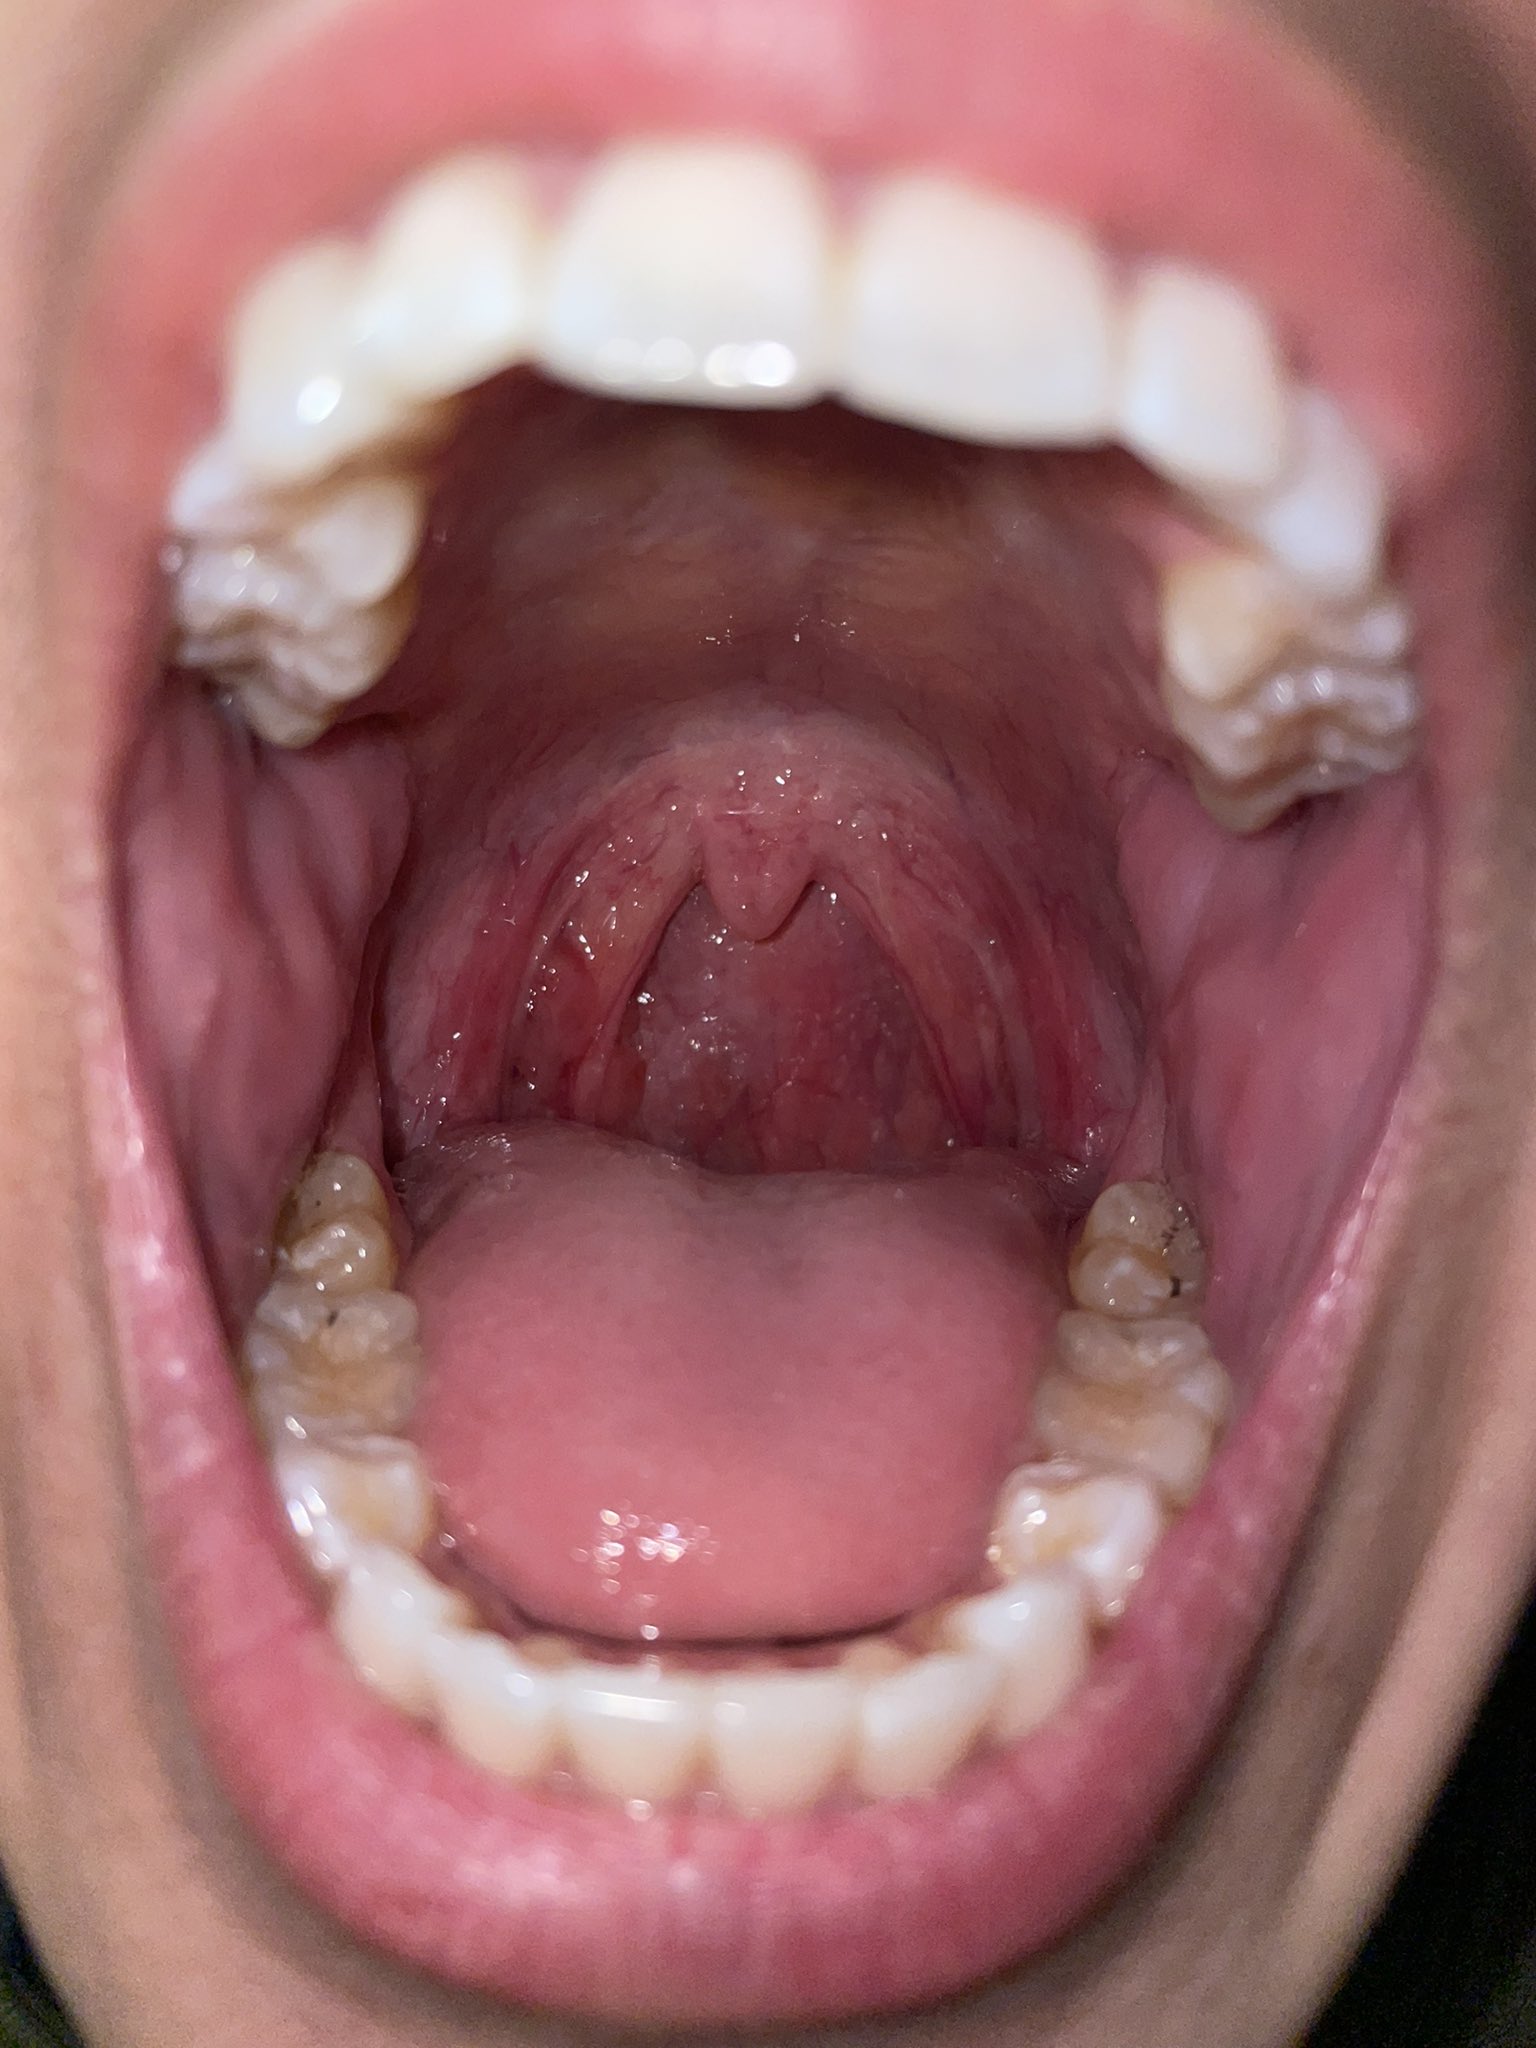

Why Does My Uvula Feel Weird . a swollen uvula can cause a sore throat, redness, trouble breathing or talking, or a choking feeling. There are many conditions that can lead to a swollen uvula, ranging from a temporary infection to genetics. If your uvula is oversized,. your uvula is also part of your gag reflex. Your stomach acid is on the move. Your symptoms are worsening even after treatment. why is my uvula swollen? Chronic acid reflux or vomiting will cause acid in. you have a fever and abdominal pain. Uvulitis refers to inflammation and. what causes a swollen uvula? an enlarged uvula is often caused by infection, an allergic reaction, or irritation from chemicals or medical. When something touches this area of your soft palate, it could induce.

Sore throat with throat swollen. Closeup open mouth with posterior Why Does My Uvula Feel Weird There are many conditions that can lead to a swollen uvula, ranging from a temporary infection to genetics. your uvula is also part of your gag reflex. a swollen uvula can cause a sore throat, redness, trouble breathing or talking, or a choking feeling. Uvulitis refers to inflammation and. Your stomach acid is on the move. When something. Why Does My Uvula Feel Weird.